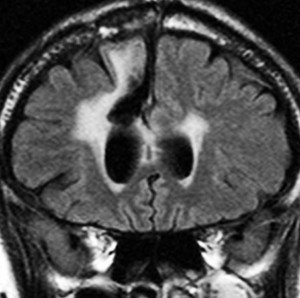

フレア画像です。左上前頭回の星細胞腫ですが,境界がとてもはっきりしていて限局性 localized single gyrus glioma です。びまん性 diffuseには見えません。IDH1の変異があり,1p/19qの欠失はないので星細胞腫グレード2です。上の例とは全く違う臨床像を示しますが,分子病理でも区別はつきません。頑張って早めに全摘出して治してしまった方がいいタイプです。再発を避けるために,supratotal resectionと言って,周囲の正常脳組織も10mmくらい余分に摘出します。

T2-FLAIR mismatch sign (T2とフレアの信号が違うこと)